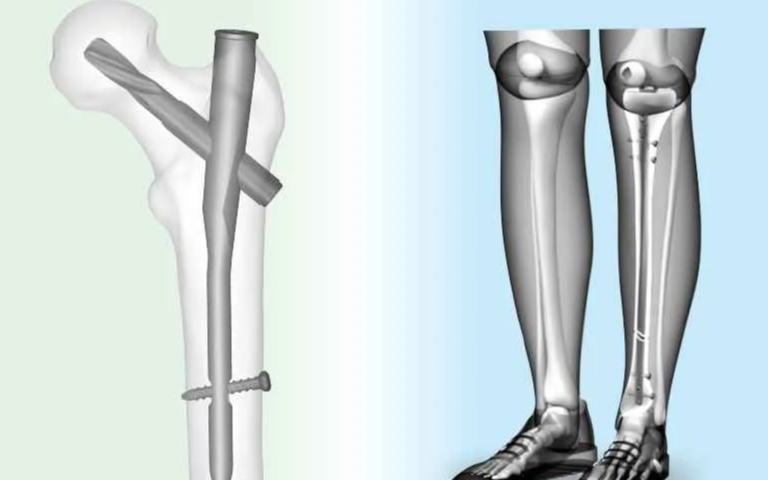

Intramedullary nailing involves placing a strong metal rod inside the hollow centre of a fractured bone, commonly the femur, tibia, or humerus. This internal support holds the bone in correct alignment while it heals, preventing deformities or improper union. Compared to traditional plates and screws, this method is less invasive, causes minimal soft tissue damage, and allows for earlier rehabilitation. Consultation with a skilled Orthopaedic Specialist in Islamabad ensures this approach is appropriate for the fracture type and patient’s overall health.

During intramedullary nailing, the surgeon makes a small incision to insert a specially designed metal rod along the central canal of the fractured bone. Screws or locking devices at each end stabilise the rod, maintaining perfect alignment during the healing process. The procedure is performed under strict sterile conditions with advanced imaging guidance, allowing an Orthopedic Surgeon in Islamabad to achieve precision and long-term stability while minimising trauma to surrounding tissues.